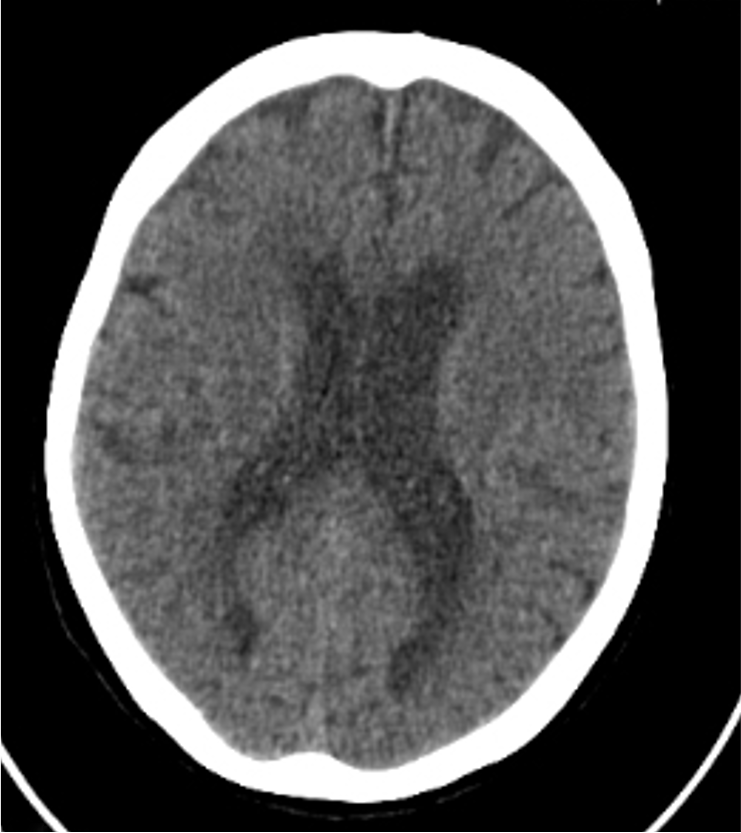

約3時間前発症の脳梗塞疑い。現症は失語。頭部単純CTで異常なし。MRI非対応埋め込み型心臓電気デバイス (CIED) 留置中の患者の為、Perfusion CT+全身アクセスルートの造影CTを施行。

本症例では急性期梗塞の診断目的のPerfusion CTをまず撮影し、5分後に血管内治療用の全身のアクセスルートを撮影した。Perfusion CTでは左前頭葉のブローカ野にMMTの延長、CBF及びCBVの低下を認めた。本症例は発症から3時間程度であったが、CBF、CBVがいずれも低下しており、非可逆性虚血を生じていた。また、左中大脳動脈に粗大な血栓はなく、血管内治療は適応外であった。